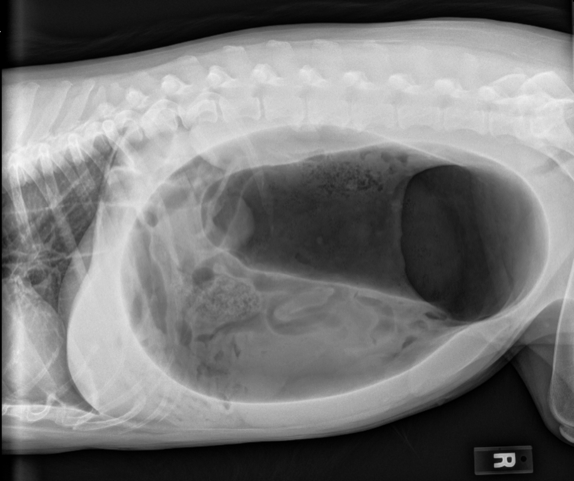

- POCUS (aFAST3): 0/4 abdominal fluid score, marked gaseous gastric distension suspected

- RLAT AXR

- Obstructive shock

- Gastric dilatation-volvulus